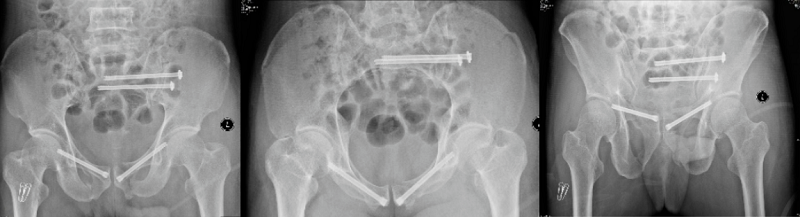

術(shù)前X線片

手術(shù)中

術(shù)后X線片

在本次科研臨床試驗中,全部22例骨盆骨折病例均順利完成了微創(chuàng)的閉合復(fù)位,驗證了智能化骨折復(fù)位機(jī)器人系統(tǒng)的術(shù)前自動手術(shù)規(guī)劃、術(shù)中實時3D導(dǎo)航及力位協(xié)同控制等創(chuàng)新功能的臨床適應(yīng)性和安全性,系統(tǒng)操作順暢,操作精度和穩(wěn)定性滿足臨床需求,取得了良好的療效。